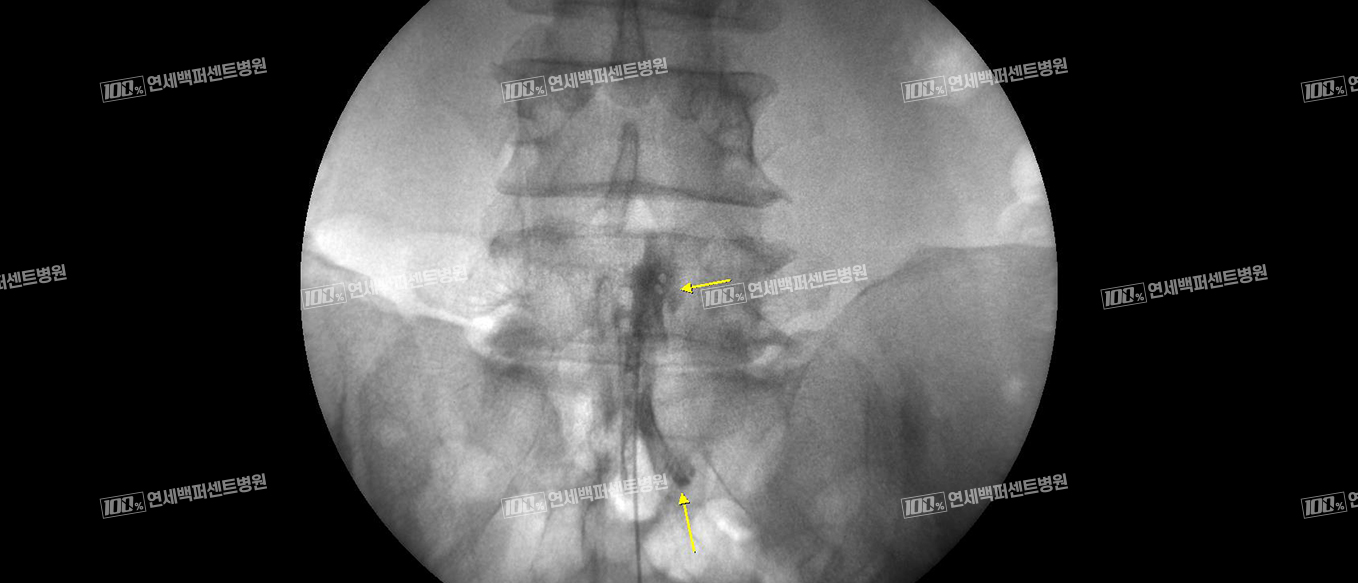

풍선 확장 경막외 신경성형술

꼬리뼈로 카테터를 삽입해 병변까지 도달시킨 뒤 카테터 끝에 달린 풍선을 확장해

협착부위를 넓히고 직접 염증 완화 및 유착방지 약물을 주입하는 시술입니다.

척추전방전위증

풍선확장술